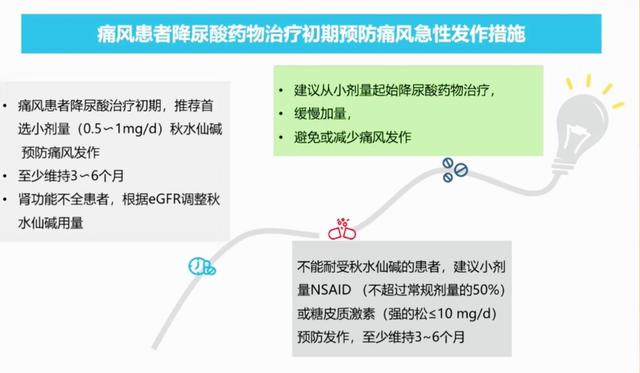

- 服用其他药物:现在我们也建议痛风患者在接受降尿酸治疗的初期,可以服用小剂量的秋水仙碱,比如每天服用0.5~1毫克的量,这样来预防可能出现的痛风反复发作,而且建议服用3~6个月的时间,如果服用秋水仙碱反应比较大,那么可以服用非甾体抗炎镇痛药(洛索洛芬钠、塞来昔布等),但是同样要减半药量服用。